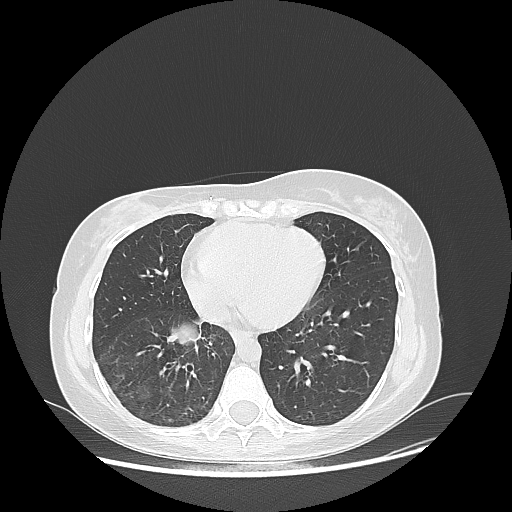

Original VENOUS CT scan

Lung window (WL -600, WW 1500 β†’ Low βˆ’1350, High +150)